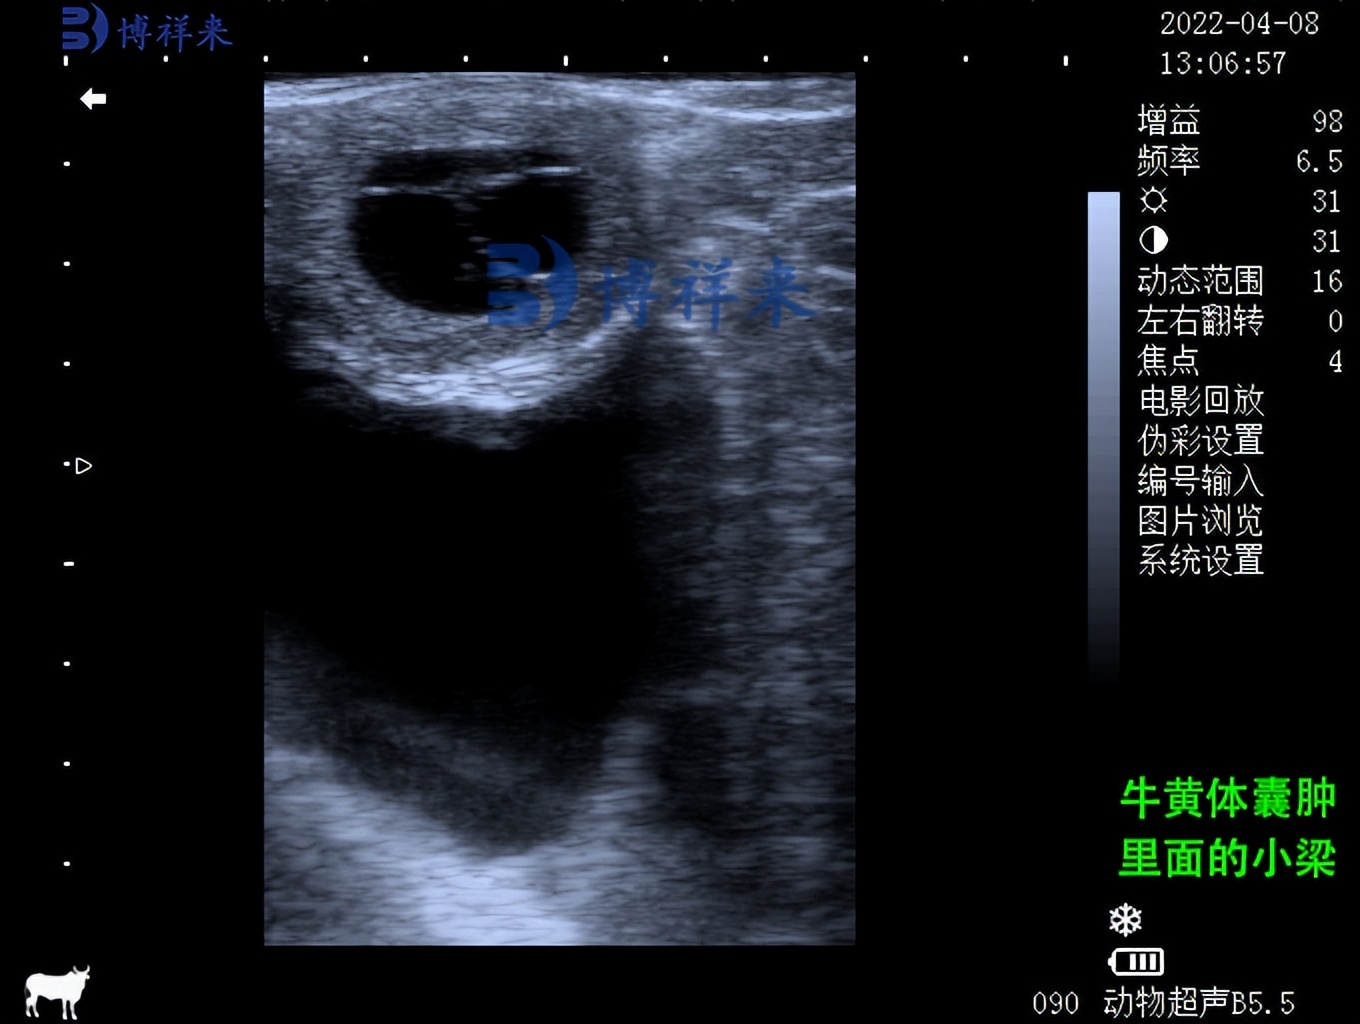

兽用B超机可检测卵巢和子宫异常

滤泡囊肿显示出大的 (25-55 mm) 非回声区,壁非常薄。 相反,黄体囊肿表现为被不同厚度(2-5 毫米)的回声组织包围的无回声区域。 在用促性腺激素释放激素治疗的囊肿奶牛中,肿壁的厚度在两周内从 2 毫米增加到 6 毫米。

牛黄体囊肿超声图像